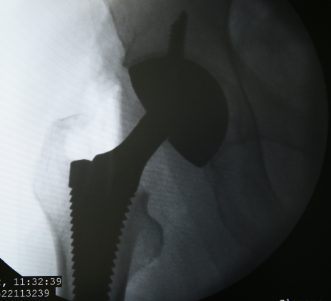

股骨头坏死是一个病理演变过程,初始发生在股骨头的负重区,应力作用下坏死骨骨小梁结构发生损伤即显微骨折以及随后针对损伤骨组织的修复过程。…「查看详情」

很多关节炎患者病情发展到了晚期,就应该做人工关节置换手术了,但很多患者都对人工关节炎置换有所顾虑和担忧,还有一个很多患者都关心的问题就是“人工关节能使用几年?”就此问题昆…「查看详情」